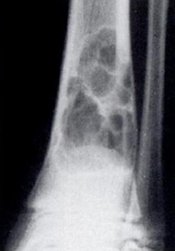

Fig 99. Fibroma no osificante.

Rx AP. Defecto fibroso cortical multiloculado, con extensión a la medular del hueso, por fibroma no osificante.